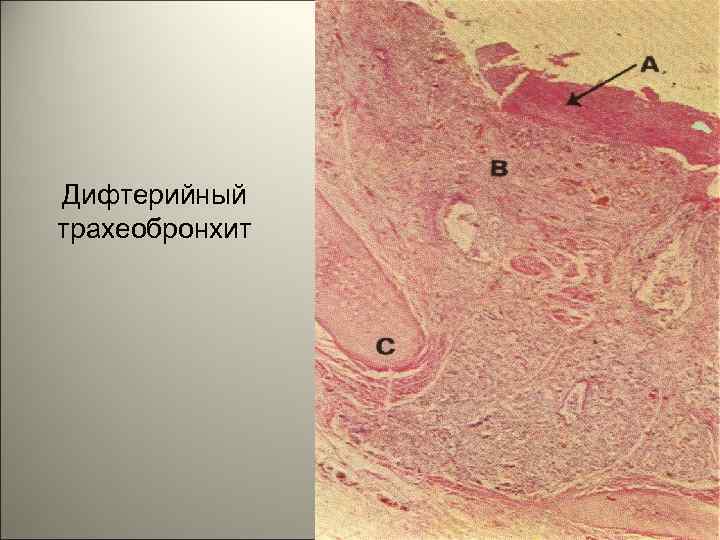

• Возбудитель — бацилла Лёффлера, вырабатывающая нейротропный экзотоксин. Преимущественная локализация воспаления — зев, гортань, носоглотка, реже бронхи, нос, наружные половые органы у девочек. 112

• Патогенез. Воротами инфекции чаще являются слизистые оболочки зева, гортани и носа. Во всех случаях возбудитель размножается в области входных ворот инфекции, а выделяемый им экзотоксин, помимо местного, оказывает также общее действие. В месте проникновения экзотоксин вызывает коагуляционный некроз эпителия, поражение сосудов (расширение, повышение проницаемости, стаз). 113

Дифтерийный трахеобронхит 122